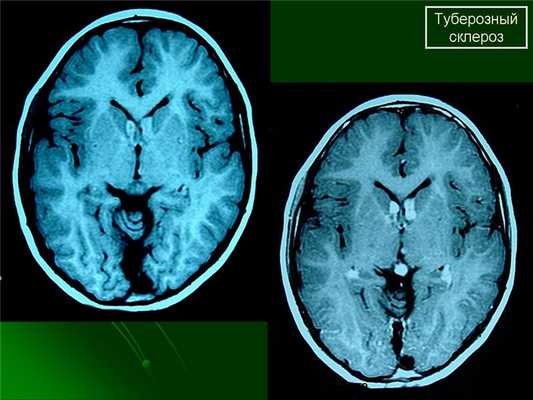

МРТ головного мозга при туберозном склерозе. Участки изменения МР-сигнала неправильной формы в коре и подкорковом белом веществе — так называемые корковые туберсы.

При подозрении на эту болезнь обязательно следует проводить МРТ головного мозга. При этом в головном мозге выявляются характерные МРТ-признаки туберозного склероза: корковые и подкорковые узлы (туберсы), субэпендимальные узелки (гамартомы), а также различные изменения белого вещества – очаговые и кистозные.

(а) МРТ, Т1-ВИ, аксиальный срез: у мальчика возрастом 13 дней хорошо демонстрируются множественные гиперинтенсивные на Т1-ВИ субкортикальные туберсы радиальные линии миграции в БВ и гиперинтенсивный субэпендимальный узел (СЭУ). Непораженное немиелиниизированное БВ имеет гипо-интенсивный сигнал.

(б) МРТ, Т2-ВИ, аксиальный срез: у того же пациента в возрасте одного года определяются СЭУ, имеющий гипоинтенсивный сигнал, и множественные гиперинтенсивные туберсы. Некоторые изменения, отчетливо визуализирующиеся на предыдущем изображении, здесь не визуализируются; некоторые туберсы, ранее не очевидные, теперь видны.